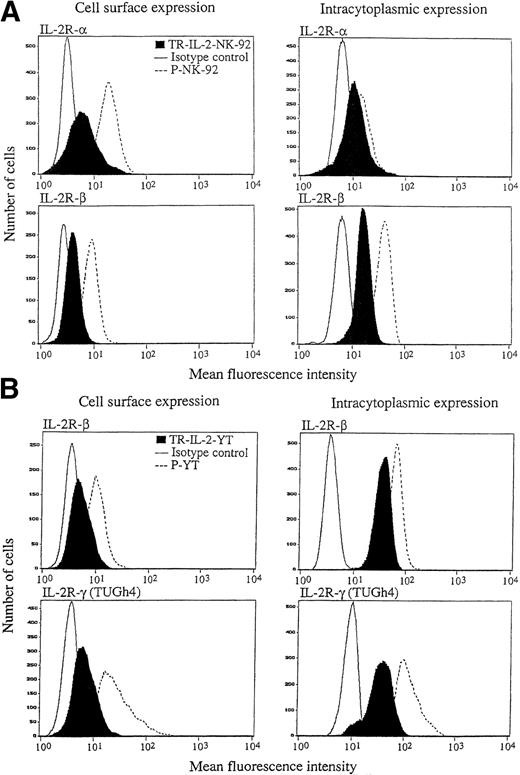

In addition, the proportion of cells in culture expressing surface and/or intracellular IL-2 was determined by both immunoperoxidase staining and flow cytometry (Fig4). Both NK-92 and YT cells expressed a minimal amount of surface-associated IL-2 detectable by flow cytometry (data for YT cells are shown in Fig 4A), and there were no differences between transduced cells and parental cells. Intracellular IL-2 protein was detectable in all transduced NK-92 (Fig 4C) and all YT cells (Fig4B), as indicated by the shift of the IL-2 peak to the right. P-NK-92 cells also contained low levels of intracellular IL-2 (NK-92 cells are IL-2–dependent), but YT cells did not. To more precisely determine the cellular localization of IL-2, immunoperoxidase or Cy5 staining was performed in the presence of brefeldin, and all TR-IL-2-NK-92 cells were found to express IL-2 protein in the Golgi zone, an indication that the protein was synthesized in the transduced cells (data not shown). In contrast, weak and diffuse expression of IL-2 protein was observed in the cytoplasm of the parental cells (not shown), perhaps due to uptake of exogenous IL-2 from the medium.

IL-2 expression in parental or IL-2 gene–transduced and selected NK cell lines. (A) and (B) Nonpermeabilized or permeabilized cells, respectively, were stained with the FITC-labeled antibody for IL-2 and examined for surface or intracytoplasmic expression of IL-2 by flow cytometry. One representative experiment of 3 performed is shown for YT cells. Similar data were obtained in 3 experiments performed on NK-92 cells. (C) Immunostaining for IL-2 in stably transduced and selected NK-92 cells (original magnification ×1,000).

IL-2 expression in parental or IL-2 gene–transduced and selected NK cell lines. (A) and (B) Nonpermeabilized or permeabilized cells, respectively, were stained with the FITC-labeled antibody for IL-2 and examined for surface or intracytoplasmic expression of IL-2 by flow cytometry. One representative experiment of 3 performed is shown for YT cells. Similar data were obtained in 3 experiments performed on NK-92 cells. (C) Immunostaining for IL-2 in stably transduced and selected NK-92 cells (original magnification ×1,000).